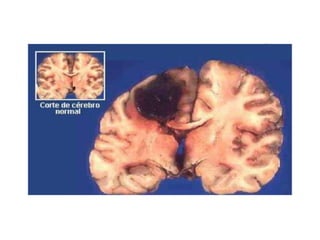

Crack Seis vezes mais potente que a cocaína, o crack tem ação devastadora provocando lesões cerebrais irreversíveis e aumentando os riscos de um derrame cerebral ou de um infarto; Porém, ao contrário do que se poderia imaginar, não são as complicações de saúde pelo uso crônico da droga,  mas sim  os homicídios que constituem a primeira causa de morte entre os usuários , resultantes de brigas em geral, ações policiais e punições de traficantes pelo não-pagamento de dívidas contraídas nesse comércio; outra causa importante são as doenças sexualmente transmissíveis, como o HIV, por exemplo, por conta do comportamento promíscuo que a droga gera .

Crack Seis vezesmais potente que a cocaína, o crack tem ação devastadora provocando lesões cerebrais irreversíveis e aumentando os riscos de um derrame cerebral ou de um infarto; Porém, ao contrário do que se poderia imaginar, não são as complicações de saúde pelo uso crônico da droga, mas sim os homicídios que constituem a primeira causa de morte entre os usuários , resultantes de brigas em geral, ações policiais e punições de traficantes pelo não-pagamento de dívidas contraídas nesse comércio; outra causa importante são as doenças sexualmente transmissíveis, como o HIV, por exemplo, por conta do comportamento promíscuo que a droga gera .